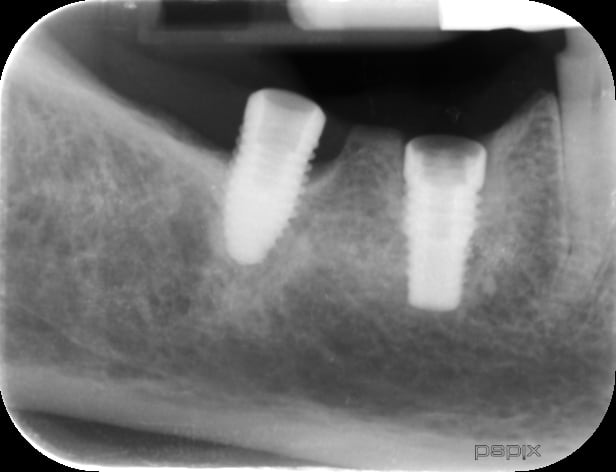

je cherche désespérément la marque de l'implant en 46.

en 46 implant violet avec pilier en trèfle a 6 feuilles

en 47, autre modèle, implant titane couleur acier, avec un pilier qui vient s'appuyer sur l'implant, mais intérieur de l'implant ressemble a un grand cône morse avec des pans. Je pense qu'un pilier provisoire a été utilisé

Celui en 46 est donc un Keystone prima connex mais en straight (droit)

celui sur 47 vu la périimplantite => bassinet.... peu importe la marque, mais il a une bonne gueule de Nobel replace CC.....

non c'est une connectique conique type Nobel CC et la forme de l'implant matche avec un replace CC